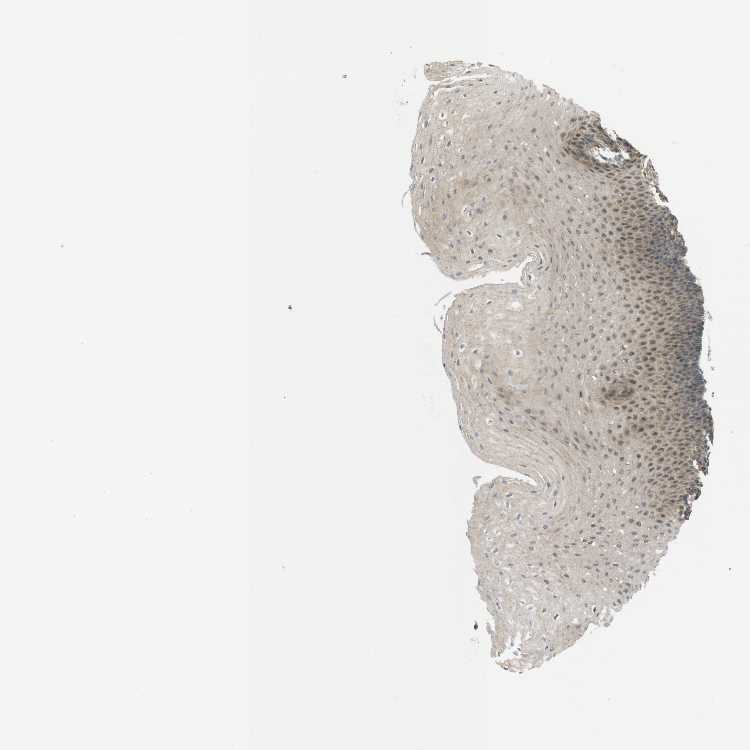

ESOPHAGUS - Antibody stainingi

Antibody staining in the annotated cell types in the current human tissue is reported as not detected, low, medium, or high, based on conventional immunohistochemistry profiling in selected tissues. This score is based on the combination of the staining intensity and fraction of stained cells.

Each image is clickable and will lead to virtual microscopy that enables deeper exploration of all samples and also displays staining intensity scores, fraction scores and subcellular localization as well as patient and tissue information for each sample.

Antibody HPA014483Antibody HPA014702

Squamous epithelial cells Not detectedMedium